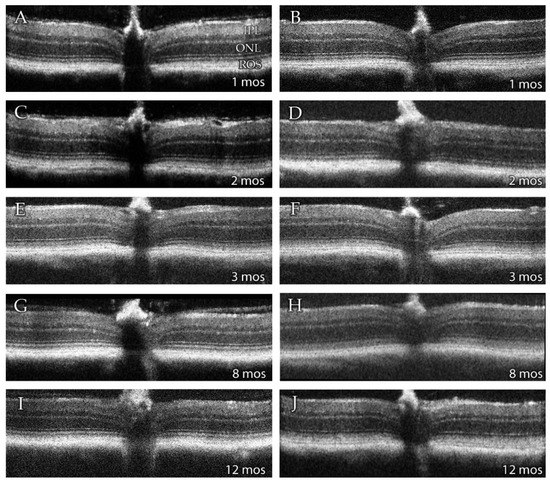

3.2. SD-OCT Analysis Reveals No Evidence for Retinal Degeneration in DhddsK42E/K42E Mice